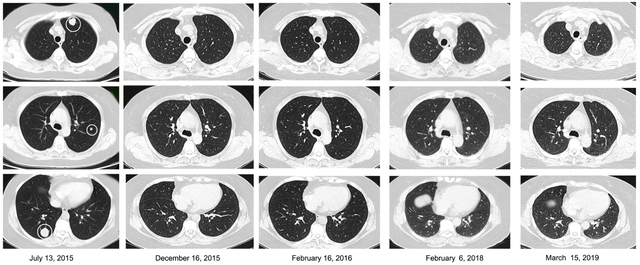

该患者于2014年8月14日诊断为子宫平滑肌肉瘤,并接受了手术。并在2014年9月18日至2014年11月11日期间接受了3个周期的辅助化疗,之后又进行了盆腔野辅助放疗。但5个月后,检查显示双肺转移。

2015年6月15日,接受了贝伐珠单抗联合化疗,遗憾的是,1个月后CT扫描显示疾病进展。于是2015年7月至2015年10月期间,该患者接受了二线化疗。幸运的是,该患者达到完全缓解(CR)状态。

由于肿瘤负荷较低,于是进行TCR基因修饰的细胞治疗。截至2019 年3月15日,该患者已经保持完全缓解状态超过3年!

图片源于细胞死亡与疾病

虽然患者在最后一轮化疗后已经出现完全缓解,但检测结果表明了si-TCR细胞在患者血液中的持久性。这些发现说明si-TCR免疫治疗是患者维持长期保持完全缓解状态的原因。